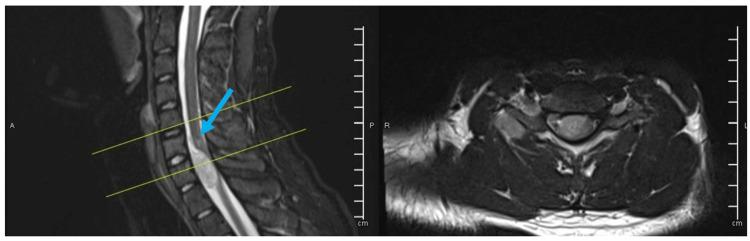

Ewing sarcoma is a rare neoplasm that mostly grows in bones or soft tissues around bones. Most cases of Ewing sarcoma occur in intra-skeletal locations (long bones, pelvis, or ribs) and rarely in extra-skeletal regions such as paravertebral or epidural space, whereas a primary intradural extramedullary Ewing sarcoma (IEES) is extremely rare. Fifty cases of primary IEES including our case were identified in the literature, so far, of which two-thirds are in the lumbosacral region, while only 12 reports described a cervical location of the tumor. Herein, we are presenting a case of C7-T1 primary IEES for a 24-year-old male, followed by a review of updated literature about the primary IEES in the cervical spine.

尤因肉瘤是一种罕见的肿瘤,主要生长于骨骼或骨骼周围的软组织。大多数尤因肉瘤病例发生于骨骼内部(长骨、骨盆或肋骨),很少发生于椎旁或硬膜外间隙等骨骼外区域,而原发性硬脊膜内髓外尤因肉瘤(IEES)极为罕见。迄今为止,文献中已报道了包括我们的病例在内的50例原发性IEES病例,其中三分之二位于腰骶部,而仅有12篇报道描述了肿瘤位于颈椎。在此,我们报告一例24岁男性C7-T1原发性IEES病例,并对颈椎原发性IEES的最新文献进行综述。